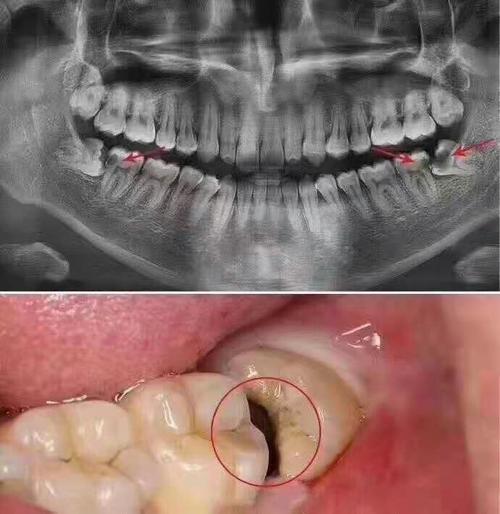

一、智齿高位近中阻生齿的特点

智齿是位于口腔后部的一组齿齿,通常在18至25岁之间开始生长。智齿的位置分为近中阻生齿和远中阻生齿,其中近中阻生齿是指智齿长在下颌骨的近中方向。

智齿的生长情况各不相同,有的智齿可以正常生长并且能够顺利地咬合到对应的上颌骨,而有的智齿则会出现生长异常,导致牙齿位置不正,甚至对周围牙齿产生影响。对于智齿高位近中阻生齿来说,由于其位置较为特殊,往往会对周围牙齿产生一定的压迫,导致口腔不适。

由于智齿高位近中阻生齿的位置较为靠近颌骨,而且与周围牙齿的位置关系较为复杂,因此其拔除难度相对较大。拔除过程中需要进行切开牙龈、骨组织切割等步骤,需要更加精细的操作技术。

智齿高位近中阻生齿的牙冠通常会部分或完全埋藏在颌骨中,这会增加拔除的难度。如果智齿牙冠部分埋藏在颌骨中,拔除时需要进行切开牙龈和骨组织的切割,才能将智齿完整地取出。

传统拔牙术是指通过手术切开牙龈、切割骨组织等方式,将智齿从颌骨中取出。这种方法需要经过术前的检查和拍片,以确定智齿的位置和生长情况,从而进行有针对性的手术操作。